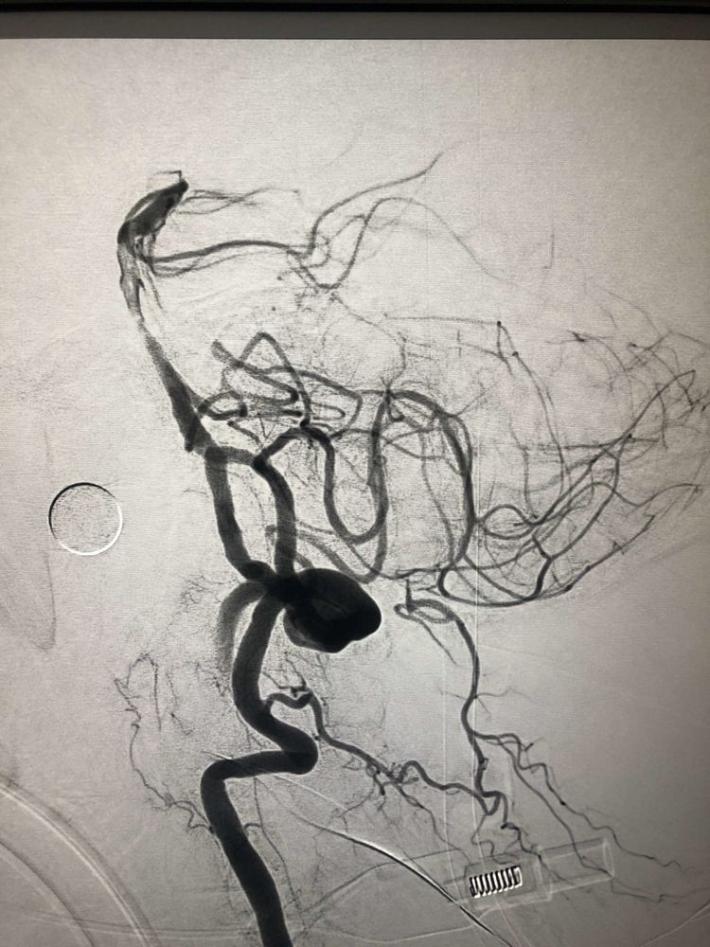

入院后75min,股动脉穿刺成功,后循环造影及右侧颈内动脉正侧位。

导丝导管通过闭塞部位,经微导管造影,证实在远端真腔内,取栓后M1重度狭窄,球囊扩张。

球囊扩张

支架植入术后前向血流通畅